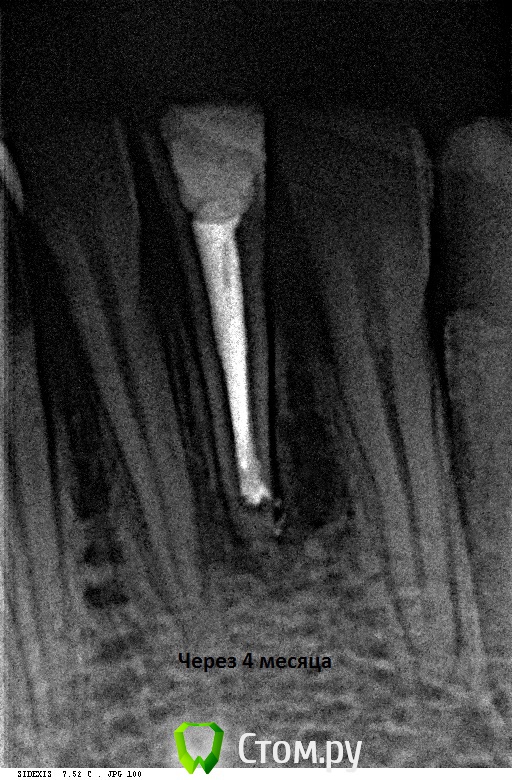

Alexandr Iv Опубликовано 21 ноября, 2014 Автор Поделиться Опубликовано 21 ноября, 2014 Контрольный осмотр через 4 месяца.Жалоб нет. 2 Ссылка на комментарий

Л Ю С Я Опубликовано 21 ноября, 2014 Поделиться Опубликовано 21 ноября, 2014 Кажется положительная динамика? Только бы не рухнул)))) Ссылка на комментарий